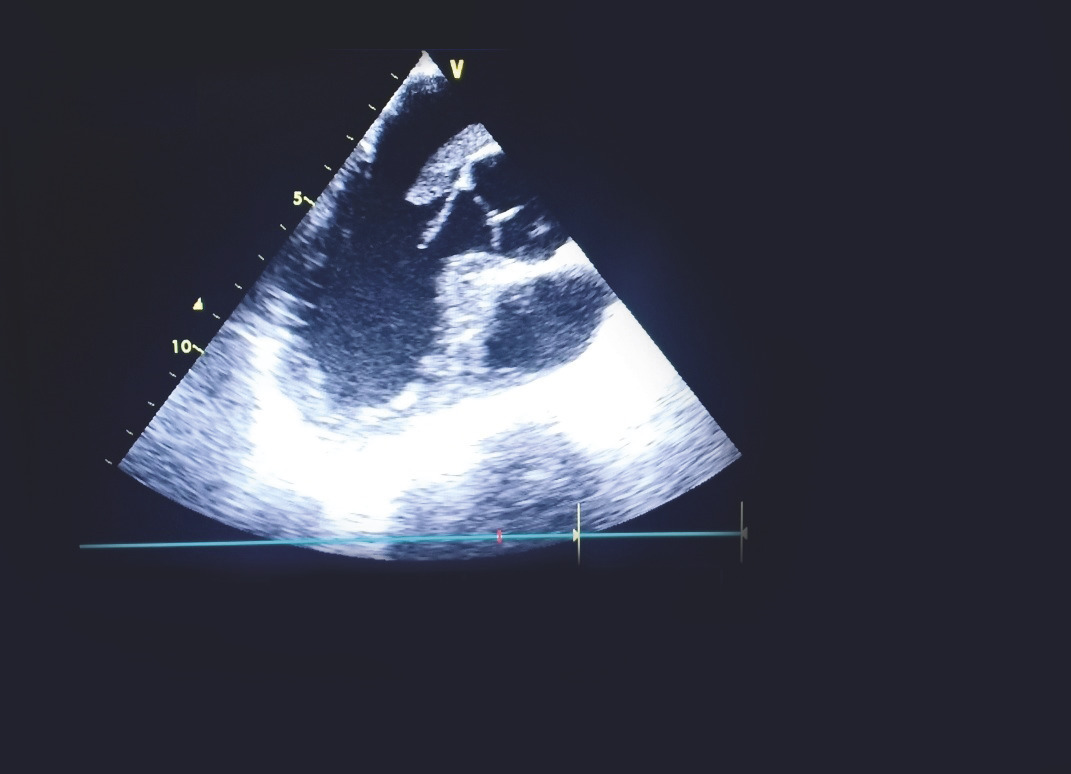

Cet homme de 37 ans était hospitalisé pour une hémiplégie gauche, 40 jours après ostéosynthèse d’une fracture du tibia droit. Son état hémodynamique et respiratoire était stable lors de son admission, avec des signes de thrombophlébite du membre inférieur droit et un rythme régulier sinusal à l’électrocardiogramme. La tomodensitométrie cérébrale montrait une plage ischémique temporo-pariétale droite. L’échocardiographie visualisait un thrombus mobile enclavé dans le foramen ovale perméable. Le patient était mis sous traitement anticoagulant ; une thrombectomie chirurgicale était réalisée avec fermeture du foramen ovale. Les suites opératoires étaient simples.

L’embolie paradoxale à travers un foramen ovale perméable est une cause rare d’accident vasculaire cérébral ischémique. Elle est due à l’embolisation systémique d’un caillot provenant de la circulation veineuse à travers le foramen ovale. Le diagnostic est posé devant la présence d’une thrombose veineuse, une preuve d’embolisation systémique et la démonstration échocardiographique d’une communication anormale entre les circulations droite et gauche.

La visualisation d’un thrombus enclavé dans le foramen ovale est exceptionnelle et augmente la mortalité et le taux de récidive ischémique liée à cette pathologie.1, 2

Le traitement curatif associe une anticoagulation efficace à une thrombectomie chirurgicale avec fermeture du foramen.